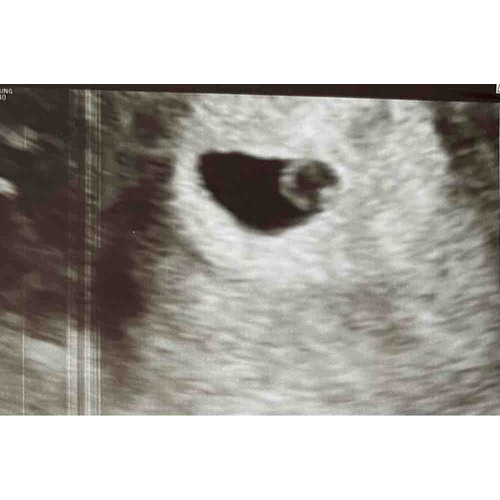

Vruchtzakje 6 Weken Miskraam. Hoe Lang Blijft Een Leeg Vruchtzakje Zitten Bij Een Miskraam? Ik ben afgelopen maandag voor nog een controle geweest (ruim een week na de miskraam) en toen was het vruchtzakje verdwenen Kreeg toen ook de boodschap: of buitenbaarmoederlijke zwangerschap, of wordt een miskraam, of je bent nog niet zo ver

Een miskraam bij 5 of 6 weken kan op verschillende manieren verlopen Nadat de miskraam volledig tot stand is gekomen of de curettage succesvol is uitgevoerd is de zwangerschap beëindigd en.

Een miskraam bij 5 of 6 weken kan op verschillende manieren verlopen Kreeg toen ook de boodschap: of buitenbaarmoederlijke zwangerschap, of wordt een miskraam, of je bent nog niet zo ver 'Ik wist niet hoe een miskraam bij zes weken eruit ziet' Een miskraam na 6 weken